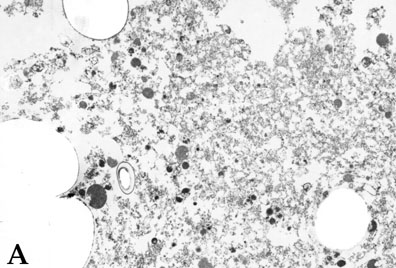

Figure 9. Enriched drusen preparations

Enriched drusen preparations from human donor eyes characterized by transmission electron microscopy (A) and Limax flavus agglutinin fluorescent labeling (B).